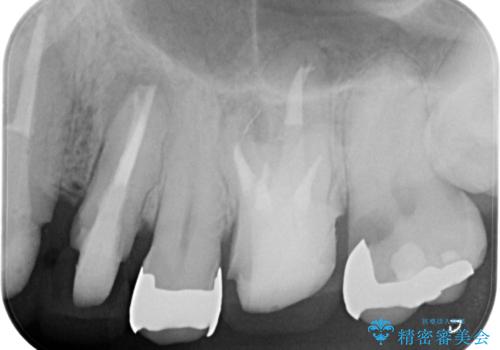

- 銀歯・虫歯・治療途中の歯を治していきたい、セラミックの歯にしたい!と希望され来院されました。

銀歯の下で再発した虫歯や、根尖病変等、多々の問題が認められましたがひとつづつ丁寧に改善し、長期的な予後の見込めるセラミック治療を行っていきます。